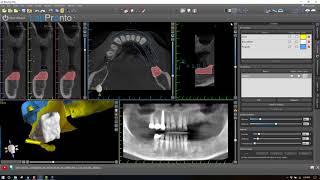

How to make a combination bone and tooth/tissue supported surgical guide video

How to make a combination bone and tooth/tissue supported surgical guide

How to make a combination bone and tooth/tissue supported surgical guide Bone Supported Surgical Guide

How to make a combination bone and tooth/tissue supported surgical guide

How to make a combination bone and tooth/tissue supported surgical guide Bone Supported Surgical Guide